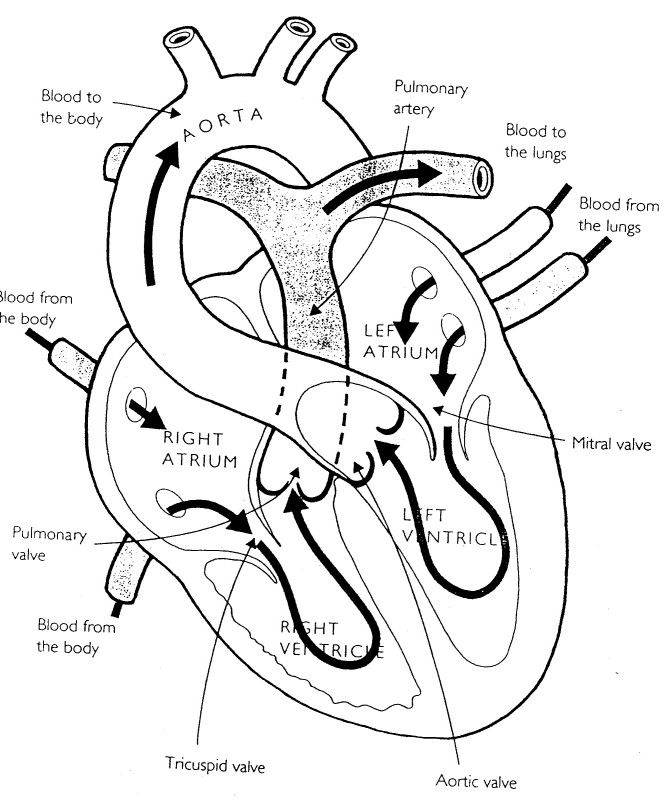

4608x3456 How To Draw The Internal Structure Of The Heart (With Pictures)

777x1024 Heart Diagram Black And White Black And White Heart Diagrams